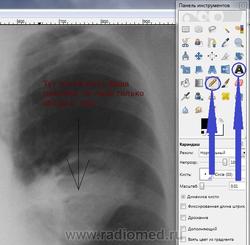

3. Надписи-стрелки тут же. Надпись - буковка "А", стрелки - рисовать карандашом (потоньше) с нажатой кнопкой Shift - тогда получаются прямые линии. В-общем, тренировка в процессе изучения)). Надписи в рамочке, предлагается в отдельном окошке введение текста, можно выбрать цвет. Лиха беда начало, примерно так)):

4. Эволюция каки в менее страшное изображение выглядит так: